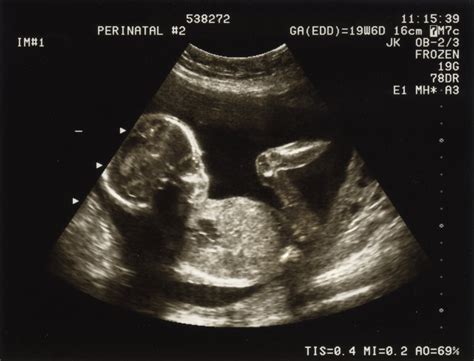

- Ecografie în obstetrică-ginecologie

- Medicină materno-fetală